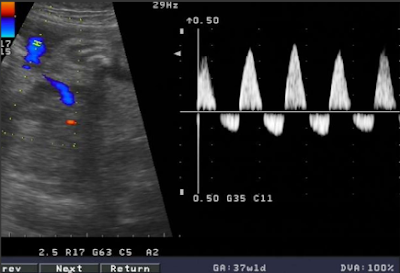

Siêu âm Doppler thai

để đánh giá:

+ Sự phát triển của thai: đo thai, đo nước ối, đánh giá bánh rau

+ Phát hiện suy thai: lượng nước ối

+ Thăm dò Doppler: ĐM rốn, ĐM não và CSNR (chỉ số não - rốn)

+ Phát hiện rau bong non: hình ảnh bánh rau, Doppler ĐMTC

+ Có thể làm ngày 2- 3 lần hay làm hàng ngày các thăm dò tình trạng thai

Các chỉ số Doppler:

- Chỉ số trở kháng ngoại biên (chỉ số Pourcelot)

RI = S

- D/S

- Tỷ số Stuart và Drumm

ISD = S/D

- Chỉ số xung Grosling

- King

PI = S- D/m

- Chỉ số tâm trương Uzan

ID = D/S x 100

- CSNR = RInão/RIrốn

Cách đo các chỉ số

Doppler của động mạch rốn:

Doppler ĐMR bệnh lý: Mất phức hợp tâm trương

Doppler ĐMR bệnh lý: Mất phức hợp tâm trương, xuất hiện dòng chảy ngược chiều

- Trong trường hợp mất phức hợp tâm trương và có dòng chảy ngược chiều hậu quả đối với thai rất xấu:

+ 98% thai suy dinh dưỡng

+ 97% phải mổ lấy thai.

+ 25% thai chết lưu trong TC.